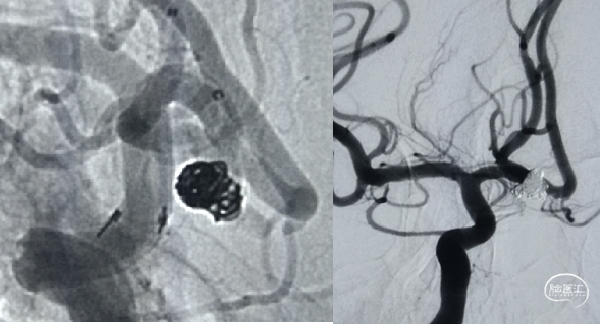

男,52岁,突发头痛3天。血泡动脉瘤

TWIN技术治疗进展性海绵窦假性动脉瘤